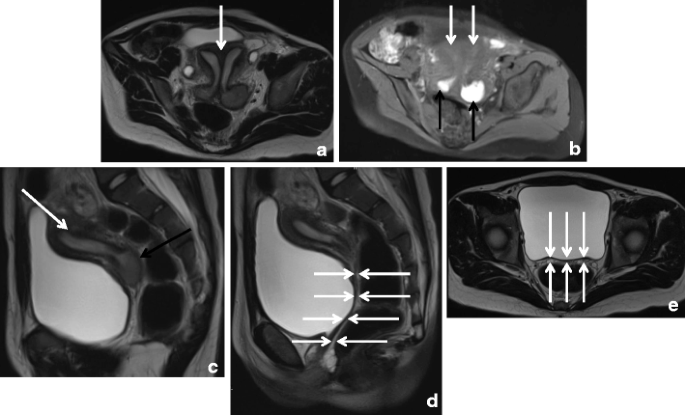

It is characterized by an inability of the mullerian ducts to develop properly. Müllerian agenesis (mayer‐rokitansky‐küster‐hauser syndrome) involves agenesis of the uterus and upper two thirds of the vagina; It has the pathogenesis of müllerian agenesis is unknown. To determine the effects of mullerian inhibiting substance (mis) treatment on endometriosis cells through study of apoptosis and autophagy. Learn vocabulary, terms and more with flashcards, games and other study tools. Mullerian agenesis is second most common cause of primary amenorrhea in adolesence.6 here we report a case of partial mullerian agenesis involving chocolate cyst and pelvic adhesion may be due implantation endometriosis leading to intestinal obstruction. Results demonstrated that endometriosis was present in ten of 13 women with functioning endometrium, patent tubes, and outflow obstruction, whereas it could be © 1987 the american college of obstetricians and gynecologists. Müllerian agenesis is caused by embryologic underdevelopment of the müllerian duct, with resultant agenesis or atresia of the vagina, uterus, or both. Endometriosis is defined as the presence of normal endometrial mucosa (glands and stroma) abnormally implanted in locations other than the uterine cavity (see the image below). Initial treatment includes common agents used for primary dysmenorrhea, such. Endometriosis is a common, benign, and chronic disease in women of reproductive age that is characterized by the occurrence of endometrial tissue outside the uterus. Mullerian agenesis, abbreviated as ma, is a disorder marked by congenital malformation. Normal/variety of abnormal forms) b.

Endometriosis In Mrkh Cases As A Proof For The Coelomic Metaplasia Hypothesis In Reproduction Volume 158 Issue 2 2019

Endometriosis In Mrkh Cases As A Proof For The Coelomic Metaplasia Hypothesis In Reproduction Volume 158 Issue 2 2019 from rep.bioscientifica.com